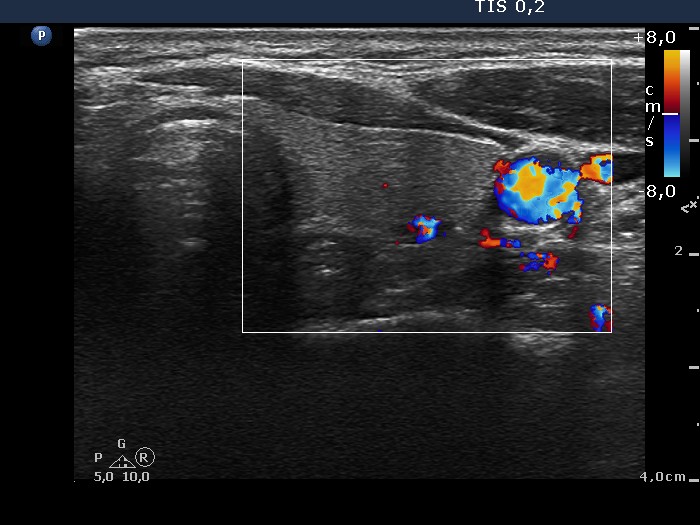

Benign nodular hyperplasia - Case 46. (ultrasonographic picture 7)

Right lobe, longitudinal scan

Left lobe, horizontal scan, color Doppler mode. There is a small vessel in the dorsal part of the lobe.